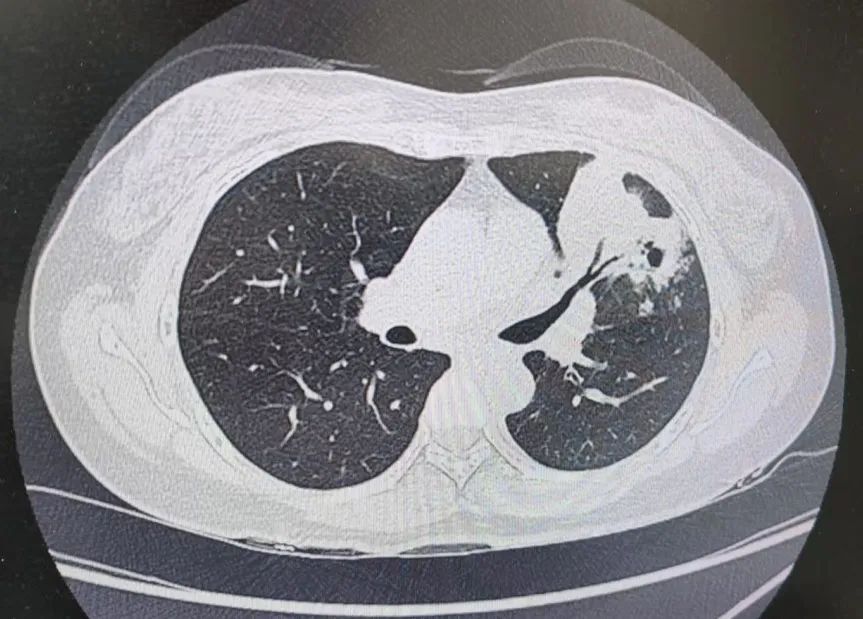

患者肺部CT影像

“一般来说,肺炎经过一周的抗感染治疗,病灶会有所吸收。但陈女士的肺部阴影纹丝不动,这种情况必须提高警惕。”宋刚主任团队立即启动了更深入的“三部精准诊断”程序:

1、支气管镜探查:快速排除气道新生物;

2、肿瘤标志物追踪:多项血清指标显著升高,直指肿瘤可能;

3、CT引导下穿刺活检:病理诊断为左肺上叶腺癌。

肺炎型肺癌,因其影像学表现与普通肺炎极为相似,临床上误诊率极高。然而确诊仅是第一步。宋刚主任当天即召集肿瘤科、病理科、影像科等多学科专家会诊,为陈女士制定个体化治疗方案。